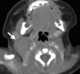

Sternocleidomastoid muscle hypertrophy

Spasmodic torticollis is an extremely painful chronic neurological movement disorder causing the neck to involuntarily turn to the left, right, upwards, and/or downwards. The condition is also referred to as "cervical dystonia". [Source: Wikipedia ]